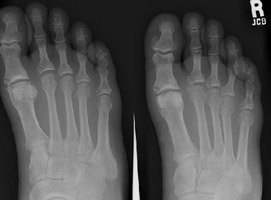

- Click on the image for a larger versionBAP radiograph of the foot demonstrates a fracture of the fourth proximal phalanx.